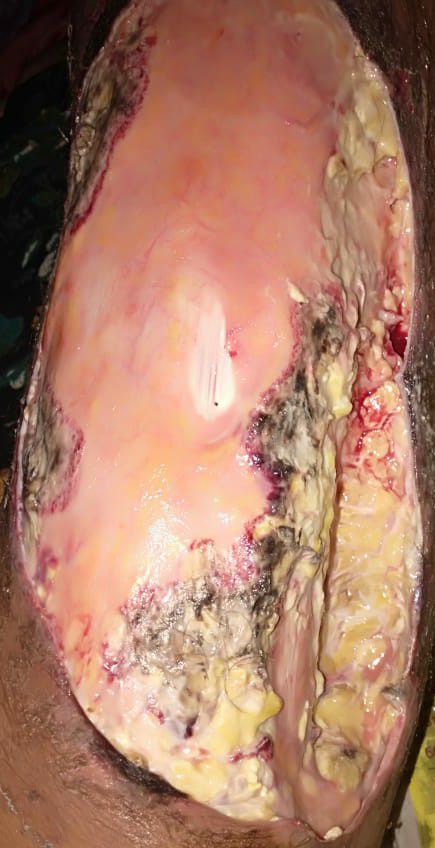

#debrament

Surgery

Thigh

Lowerlimb